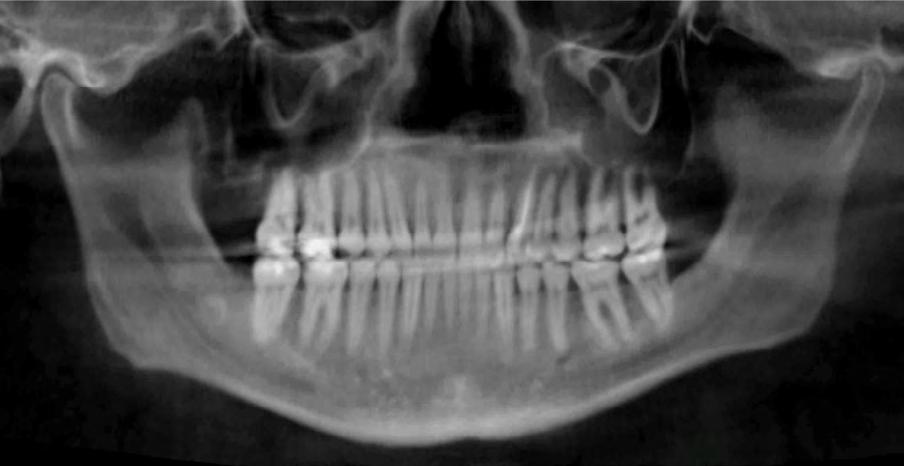

Clinical evaluation showed a mild Class III skeletal pattern with a constricted maxilla, mildly dolichofacial and straight

profile (Figure 1). Full adult dentition was present with all third molars extracted. Maxillary and mandibular incisors were normoclined. The maxillary midline coincided with the facial midline, and the mandibular midline was 2 mm to the right of the facial midline. There was a 2 mm to 5 mm lateral open bite on the right side from the second molar to the lateral incisor, and the maxillary occlusal plane was canted to the left of the interpupillary line. A lateral tongue thrust into the open bite was noted on swallow.

The right side was in posterior crossbite and there was an edge-to-edge anterior bite with wear on the maxillary central incisors. Mild gingival recession was noted, but soft tissue was generally within normal limits. CBCT analysis found no radiographic evidence of osteoarthritis in the TMJ joints, nor osseous or apical pathology involving the maxillary or mandibular teeth. His airway was not constricted. Initial report from the myofunctional therapist indicated that the patient never developed a mature swallow sequence and had a bilateral posterior tongue thrust.

Figure 1. Initial records.